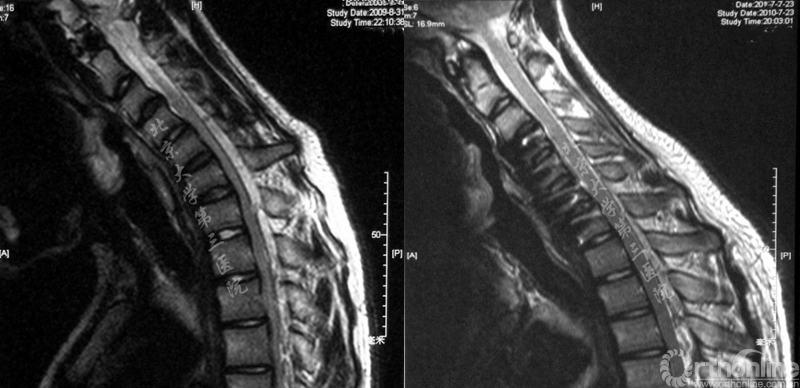

术前屈曲位核磁示下颈段脊髓前方受压 术后1年随访屈曲位核磁